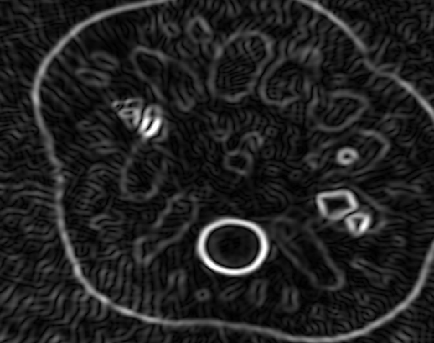

We implemented the methods 1 and 2 in Matlab and tested them on the x-ray CT data of a lotus root, cf. [7]. In our experiments we converted the fan-beam data to a parallel-beam data using Matlab function fan2para and downsampled this data in order to simulate angular undersampling. Thereby, we used 738 equispaced samples in the s𝑠s-variable and 363636 evenly distributed angles in [0,π)0𝜋[0,\pi). For our implementations, we used the Matlab functions radon and iradon as numerical realizations of the Radon transform, the inverse Radon transform and the backprojection operator. For the minimization of the 1superscript1\ell^{1}-functional (9), we implemented the iterative soft thresholding algorithm, cf. [8].

The CT data and the corresponding FBP reconstruction are shown in Fig. 1(a) and 1(d). It can be clearly observed that the FBP reconstruction contains many undersampling artifacts (streaks) that could complicate the detection of edges in that image. Hence, we calculated the gradient directly from CT data using the methods 1 and 2, where we chose the parameters based on visual inspection of edge detection results. These are given in the caption of Fig. 1.

Figure 1: Rebinned CT data of a lotus root 1(a) and the corresponding FBP reconstruction 1(d) from an angular range given by [0,π)0𝜋[0,\pi) and 363636 evenly distributed angles, cf. [7]. The magnitude of the gradient |fε|subscript𝑓𝜀\left|\nabla f_{\varepsilon}\right|, in 1(b) and 1(c), and the corresponding edge detection results using the Canny algorithm, see 1(e) and 1(f).

In Fig. 1(b) and 1(e) one can see that the Gaussian smoothing cannot compensate for the undersampling artifacts and, thus, many edges in the edge map are not coming from actual image features. However, the 1superscript1\ell^{1}-regularization successfully reduces the number of artifacts and detects the edges more reliably, as can be seen in Fig. 1(c) and 1(f). In other experiments we also observed that the method 2 outperforms the method 1 whenever the CT data was not sampled properly. For dense angular sampling, we found that both methods produce similar edge detection results.